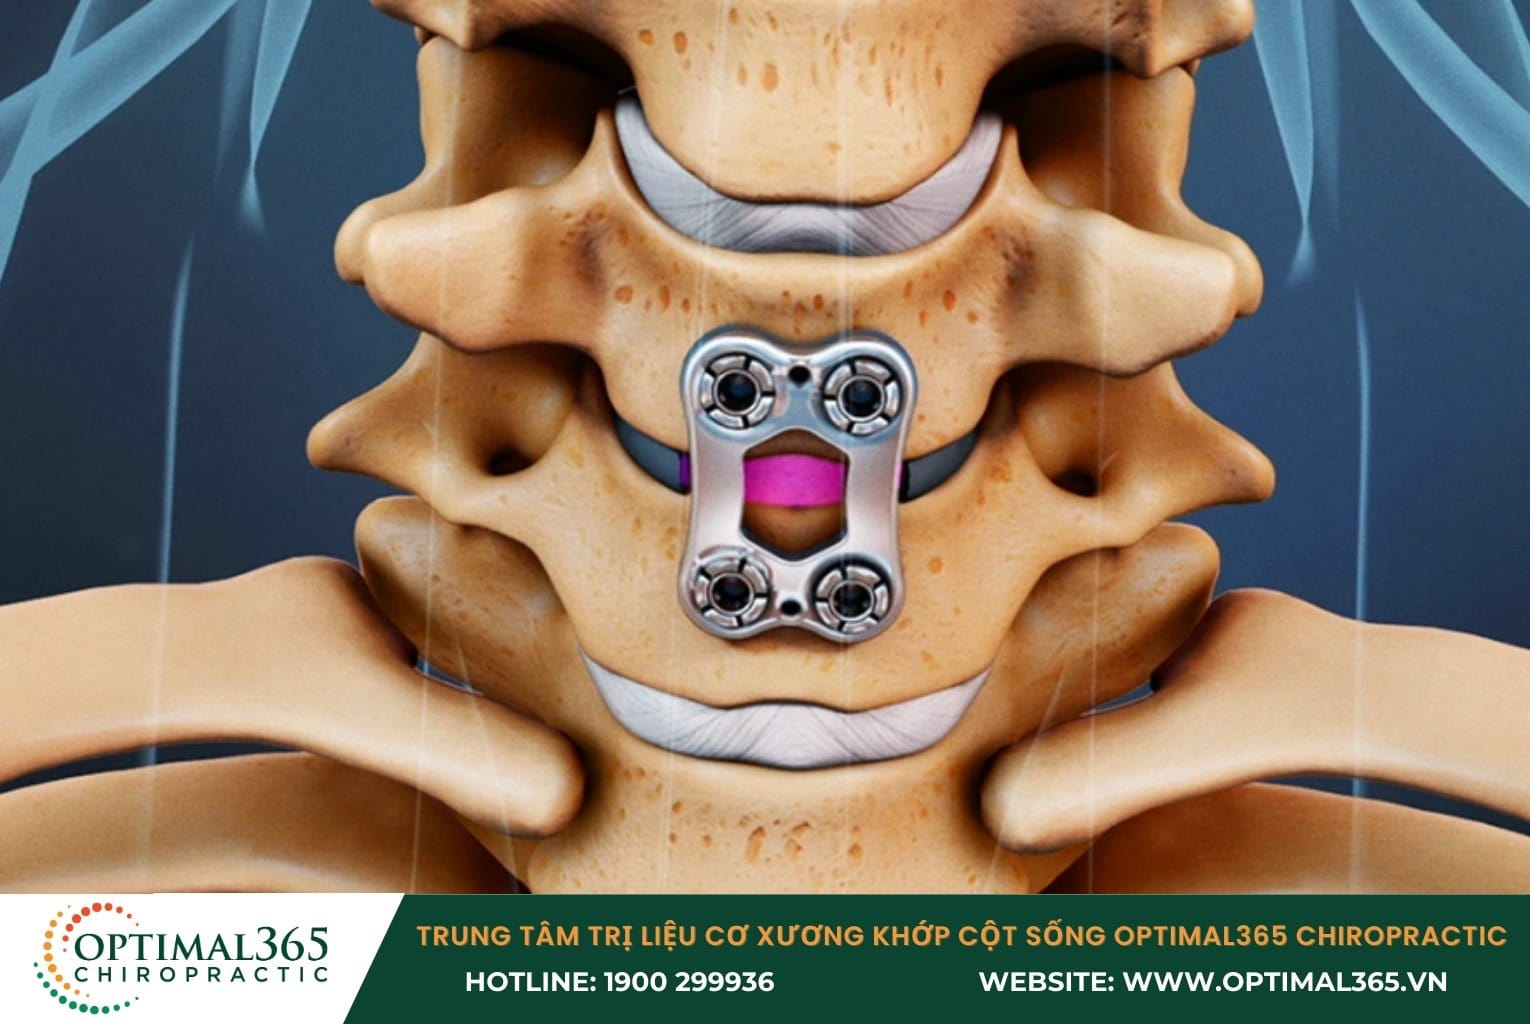

Phẫu thuật

Theo hướng dẫn điều trị của Viện Y tế Quốc gia Anh (NICE) khuyến nghị rằng phẫu thuật chỉ nên được xem xét sau khi các phương pháp điều trị bảo tồn không mang lại hiệu quả trong khoảng thời gian từ 6 đến 8 tuần. Theo đánh giá của NICE, chỉ khoảng 5% bệnh nhân cần đến phẫu thuật khi:

- Các phương pháp điều trị trước đó không phát huy tác dụng

- Thoát vị đĩa đệm gây hội chứng chùm đuôi ngựa, phần chân tê liệt, rối loạn bàng quang, không thể kiểm soát đại tiểu tiện, mất cảm giác vùng hậu môn và bộ phận sinh dục.

- Loét dạ dày, tổn thương nội tạng do lạm dụng quá nhiều thuốc giảm đau